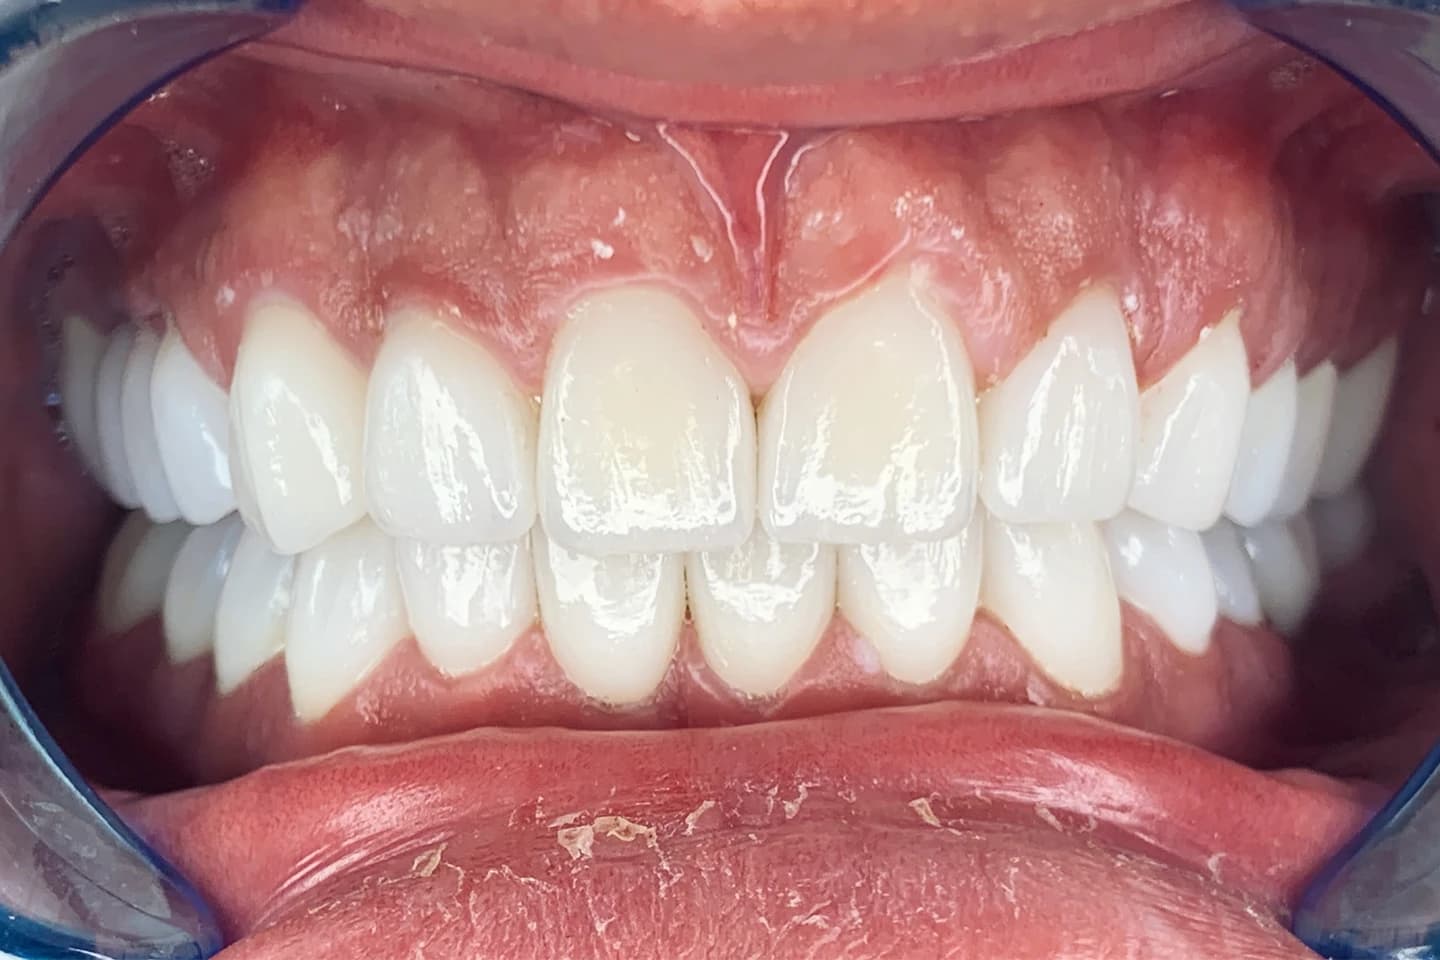

Osmeh i oblik zuba slike - pre i posle

Stomatološka ordinacija Marco Dental Tourism svakodnevno stvara neverovatne transformacije osmeha. Pogledajte galeriju naših radova i uverite se u moć stomatologije!

Želimo i vama da pomognemo da postignete savrršen osmeh kada su u pitanju položaj i oblici zuba. Zato smo prikupili inspirativne priče i fotografije zuba naših pacijenata, koje će vam pokazati šta je sve moguće uz stručnost i posvećenost našeg tima.